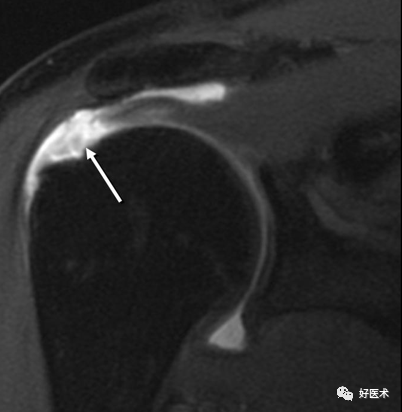

撞击综合征

当肩关节处于外展体位时,尤处于60°~120°时肩峰下空间缩小且肩腱袖刚好从中穿过,此时由于一些解剖结构病变引起冈上肌出口(肱骨头上方和肩峰下方间的间隙) 狭窄,即压迫肩峰下滑囊和/ 或冈上肌腱,引起以有肩部和上臂疼痛为特征的临床征候群。

肩袖、肱二头肌长头腱、肩峰下滑囊、喙肩弓、肩峰和肱骨头在综合征中起重要作用。

(1)肩峰下撞击综合征

1)病因:肩峰或喙肩弓结构异常、退行性变、创伤。

5)MRI表现

肩峰的形状:

Ⅰ型:扁平型;

Ⅱ型:弓型;

Ⅲ型:钩型

肩峰下滑囊及肩袖的改变:

Ⅰ型:肩峰下滑囊炎,滑囊增厚而冈上肌及其肌腱信号正常

Ⅱ型:

Ⅲ型: 冈上肌回缩及冈上肌腱异常信号,提示肩袖完全撕裂

肩锁关节骨质增生,冈上肌腱上部信号增高

肩峰下缘倾斜,肌腱撕裂

典型撞击伴冈上肌腱撕裂